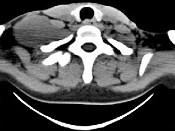

问题 女,47岁,下颈部触及一包块约5年余,CT如图所示,最可能诊断为()

选项 A.滑膜肉瘤 B.血管瘤 C.神经鞘瘤 D.副神经节瘤 E.巨淋巴结增生症

答案 C